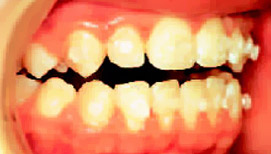

Ealsto-Finisher: Finisher берет на себя трудную задачу: точную доводку в конце лечения

Традиционные позиционеры утратили свою первоначальную задачу закрытия трем между зубами после снятия колец, т.к. брекеты, фиксируемые на зубах без колец, не оставляют после себя трем. Но заключительный этап лечения несъемными аппаратами зачастую более трудоёмок, чем предваряющие ему большие перемещения зубов на этапах нивелирования и выравнивания (рис. 1-3).

Рис.1: К окончанию лечения бугрово-фиссурные контакты не достигнуты.

Elasto-Finisher изготавливается из высокоэластичного Silasto 50. Этот материал отличается особо высокой прочностью на растяжение и при деформациях. Такие благоприятные характеристики имеют только силиконы, вулканизированные при высоких температурах.

Рис.2: Set-up визуализирует цель лечения.

Вертикальное перемещение клыков, достижение их смыкания по 1 классу, а также восстановление направляющей функции клыков, как фактор долговременной стабильности результата, составляют значительную часть времени лечения. Нетерпеливые пациенты зачастую недопонимают этого.

В отличие от лечения с помощью обычного позиционера, который изготавливается после демонтажа несъемного аппарата, при использовании Elasto-F inisher на зубах остаются брэкеты и кольца на молярах. До изготовления матрицы для дублирования моделей снимают только ортодонтические дуги и лигатуру, поскольку они не должны быть вплавлены в Elasto-Finisher. Достаточно заблокировать весь ряд зубов с помощью непрерывной лигатуры в виде восьмерки.

Рис.3: Брекеты и кольца были сняты спустя 10 недель, но пациент продолжал носить аппарат по ночам в течение одного года.